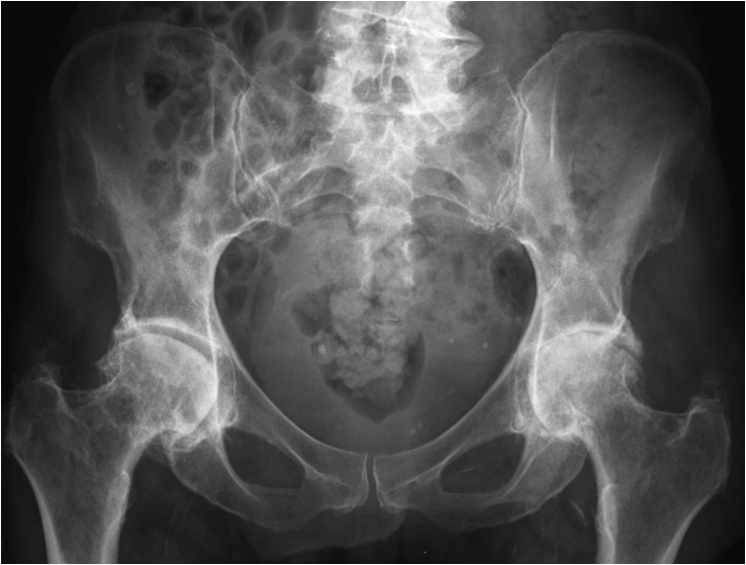

Fig. 13. A) Knee joint with degenerative changes. Note the sclerotic medial tibial plateau and joint space narrowing. A small osteophyte is seen on the medial femoral condyle. B.) Pelvis with marked degeneration of both hip joints. The right femoral head shows lateral osteophyte formation and is deformed. The joint space is narrow with increased subchondral sclerosis of the acetabular roof. The left hip has a marked joint space narrowing and lateral osteophyte formation. The femoral head shows increased density due to sclerotic areas and irregularity.